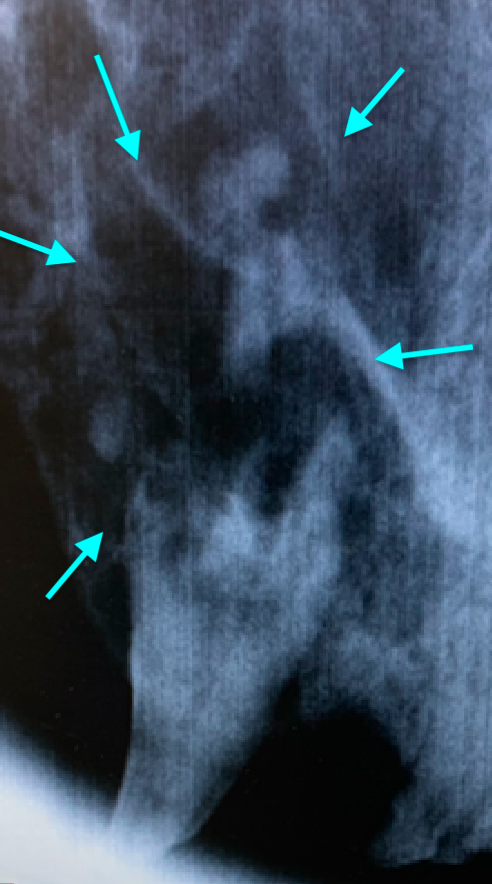

Резорбция зубов развивается вторично на фоне активности многоядерных одонтокластов, которые разрушают твердые ткани зуба. Как правило, процесс начинается в цементе на боковой поверхности корня в любом месте, а затем распространяется на дентин апикально и/или коронально.При резорбции, начинающейся на поверхности корня, в глубине альвеолы, процесс замещает периодонтальную связку и корень костно- или цементоподобной тканью. При резорбции, которая прогрессирует в сторону коронки, потеря дентина и эмали обнажает резорбцию в полости рта. Затем возникает воспаление окружающих тканей, что приводит к повышенной чувствительности. Многие невоспалительные поражения не прогрессируют – процесс остается апикальнее цементно-эмалевой границы (фото 5).

Повреждения, которые начинаются вблизи цементно-эмалевой границы, быстро подвергаются воздействию среды полости рта, где они контаминируются и воспаляются. Существует предположение о том, что эти поражения вызваны накоплением бляшек, воспалением и высвобождением цитокинов и липополисахаридов, которые стимулируют миграцию кластических клеток в эту область. Затем резорбция зуба распространяется вниз по корню, инфицируя периодонтальную связку и предотвращая замещение утраченных твердых тканей материалом, подобным кости или цементу (фото 6).